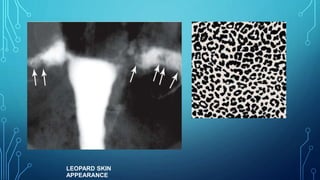

LEOPARD SKIN

APPEARANCE

• #43 Multiple rounded filling defects following intraluminal granuloma formations within the hydrosalpinx, resembling a " leopard skin" appearance [arrows]